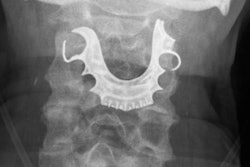

Advanced uses for dental x-ray such as prosthetics, implants, and orthodontics require a clearer view of the patient's physiology, driving demand for conebeam CT, according to the report. In fact, revenue from shipments of conebeam CT equipment accounted for an estimated 27% of annual dental x-ray equipment shipments in 2012. Shipments are predicted to rise to more than 30% in 2017.